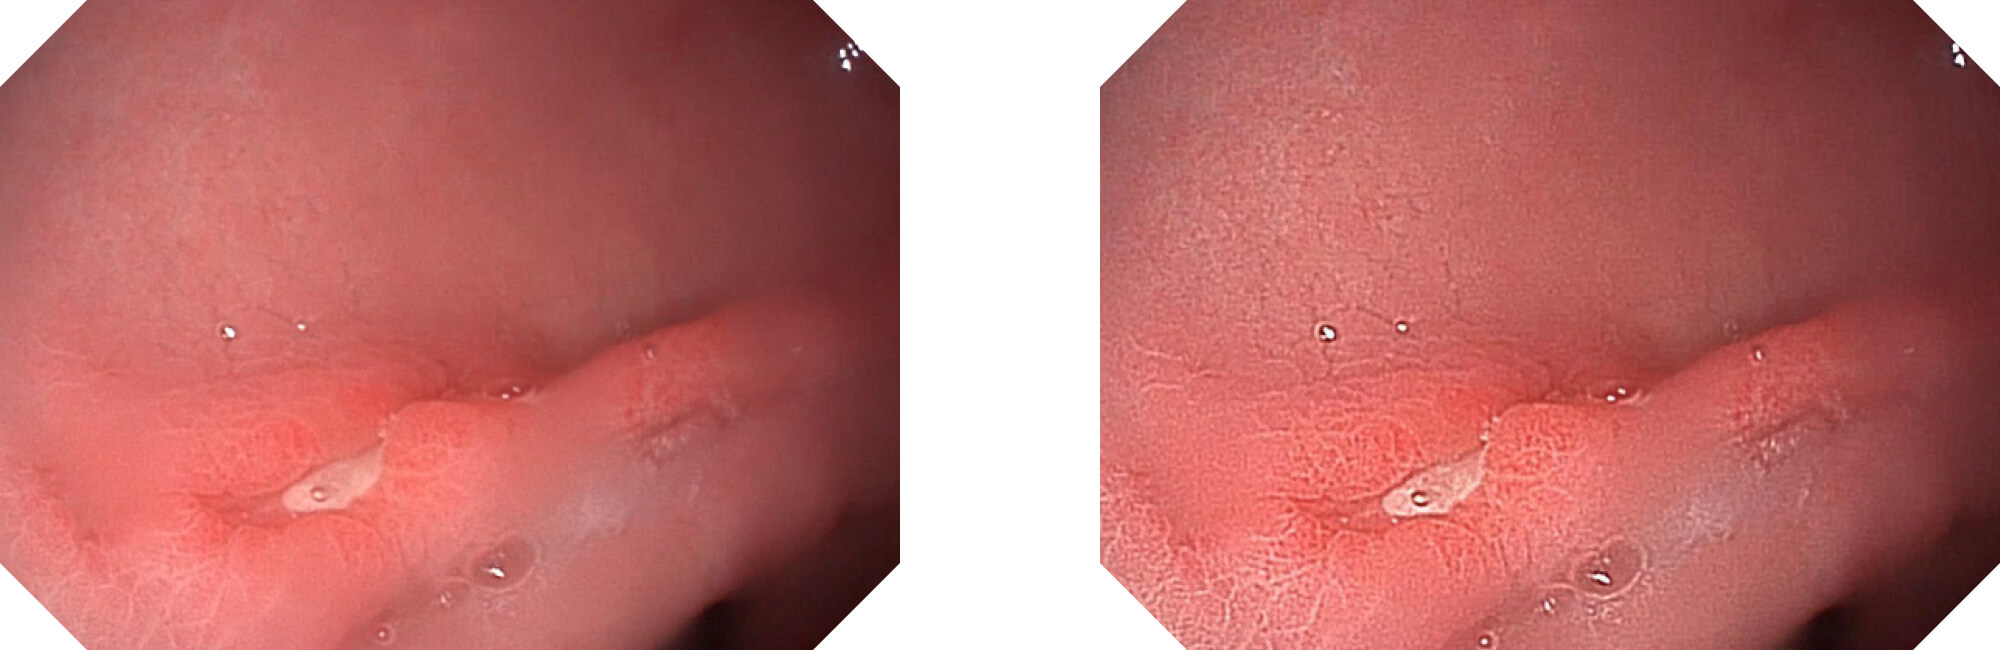

光电复合染色成像

(Versatile Intelligent Staining Technology)

利用了血红蛋白在不同波长吸收下系数不同的原理,设计的一种光学域滤波和数字域滤波结合的染色技术,既保证了图像亮度,又可增强黏膜血管的对比度,充分凸显早期病变的细微结构变化,为临床疾病的观察诊断提供更丰富的参考信息。